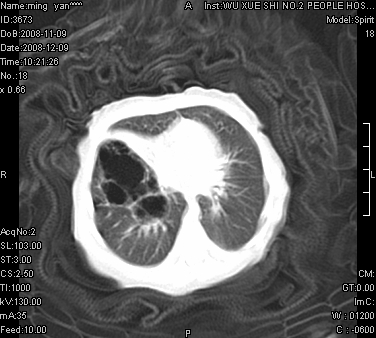

女.30天.咳嗽.喘3天.系三胞胎

考虑右肺下叶先天性肺囊肿,不除外合并右中叶肺发育不全

伴双肺感染

考虑右肺下叶先天性多发性肺囊肿可能。

考虑右肺下叶肺囊肿伴感染,右中叶节段实变或发育不全

这是一个先天性囊性腺瘤样畸形(congenital cystic adenomatid malformation,ccam),属于先天性肺发育异常,最近国外文献重新命名为先天性肺气道畸形(congenital pulmonary airway malformation,cpam),根据发生部位和畸形组织与气管、支气管的关系分成五型。本病以1岁以下婴儿多见,男性多于女性。病因为终末呼吸单元的异常增殖,形成多囊状结构。国内根据影响和病理表现分三型:ⅰ型为单个或多个大囊肿,直径大于2cm;ⅱ型为多个小囊肿,直径小于2cm;ⅲ型为大的非囊肿性病变,但显微镜下观察可见肿块由多发小囊组成(直径小于2mm)。本病可发生于肺内任何一部分,单侧肺占95%,中叶病变相对较少。